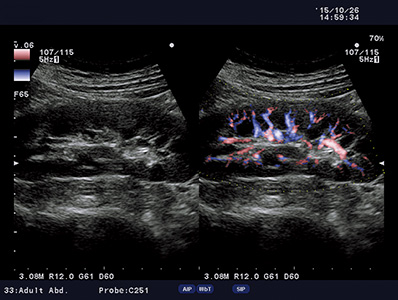

Real-time B- and Color Flow modes can be displayed side-by-side, offering an easier anatomical interpretation of blood flow.